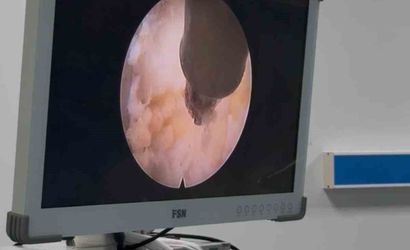

ADÜ Hastanesi'nde Tam Kapalı (Full Endoskopik) Lomber Disk Ameliyatları Başladı

Aydın Adnan Menderes Üniversitesi Hastanesi'nde Beyin ve Sinir Cerrahisi Anabilim Dalı, Aydın'da ilk kez full endoskopik lomber disk ameliyatlarını uygulamaya başladı; minimal invaziv ve hızlı iyileşme sunuyor.

Aydın Adnan Menderes Üniversitesi Hastanesi bünyesinde, Beyin ve Sinir Cerrahisi Anabilim Dalı tarafından Aydın'da ilk kez full endoskopik lomber disk ameliyatları başarıyla uygulanmaya başlandı.

Halk arasında tam kapalı bel ameliyatı olarak bilinen bu uygulama, minimal invaziv cerrahi teknikleri arasında yer alıyor. Full endoskopik yöntemle işlemler yalnızca birkaç milimetrelik kesiler üzerinden gerçekleştirilerek çevre dokulara verilen zarar en aza indiriliyor.

Bu yaklaşım, ameliyat sonrası daha az ağrı, hastanede yatış süresinin kısalması, günlük yaşama ve işe daha hızlı dönüş ile enfeksiyon ve komplikasyon risklerinin azalması gibi avantajlar sağlıyor. Çoğu hasta ameliyatın ardından kısa sürede mobilize olabiliyor ve hızlı bir iyileşme süreci geçiriyor.

Her hastada uygun olmayan bu yöntem, uygun hasta grubunda başarıyla uygulanabiliyor. Hastane, hasta güvenliğini ve bilimsel gelişmeleri esas alan yaklaşımıyla sağlık hizmetlerinde yenilikçi ve çağdaş tedavi yöntemlerini uygulamaya devam etmektedir.